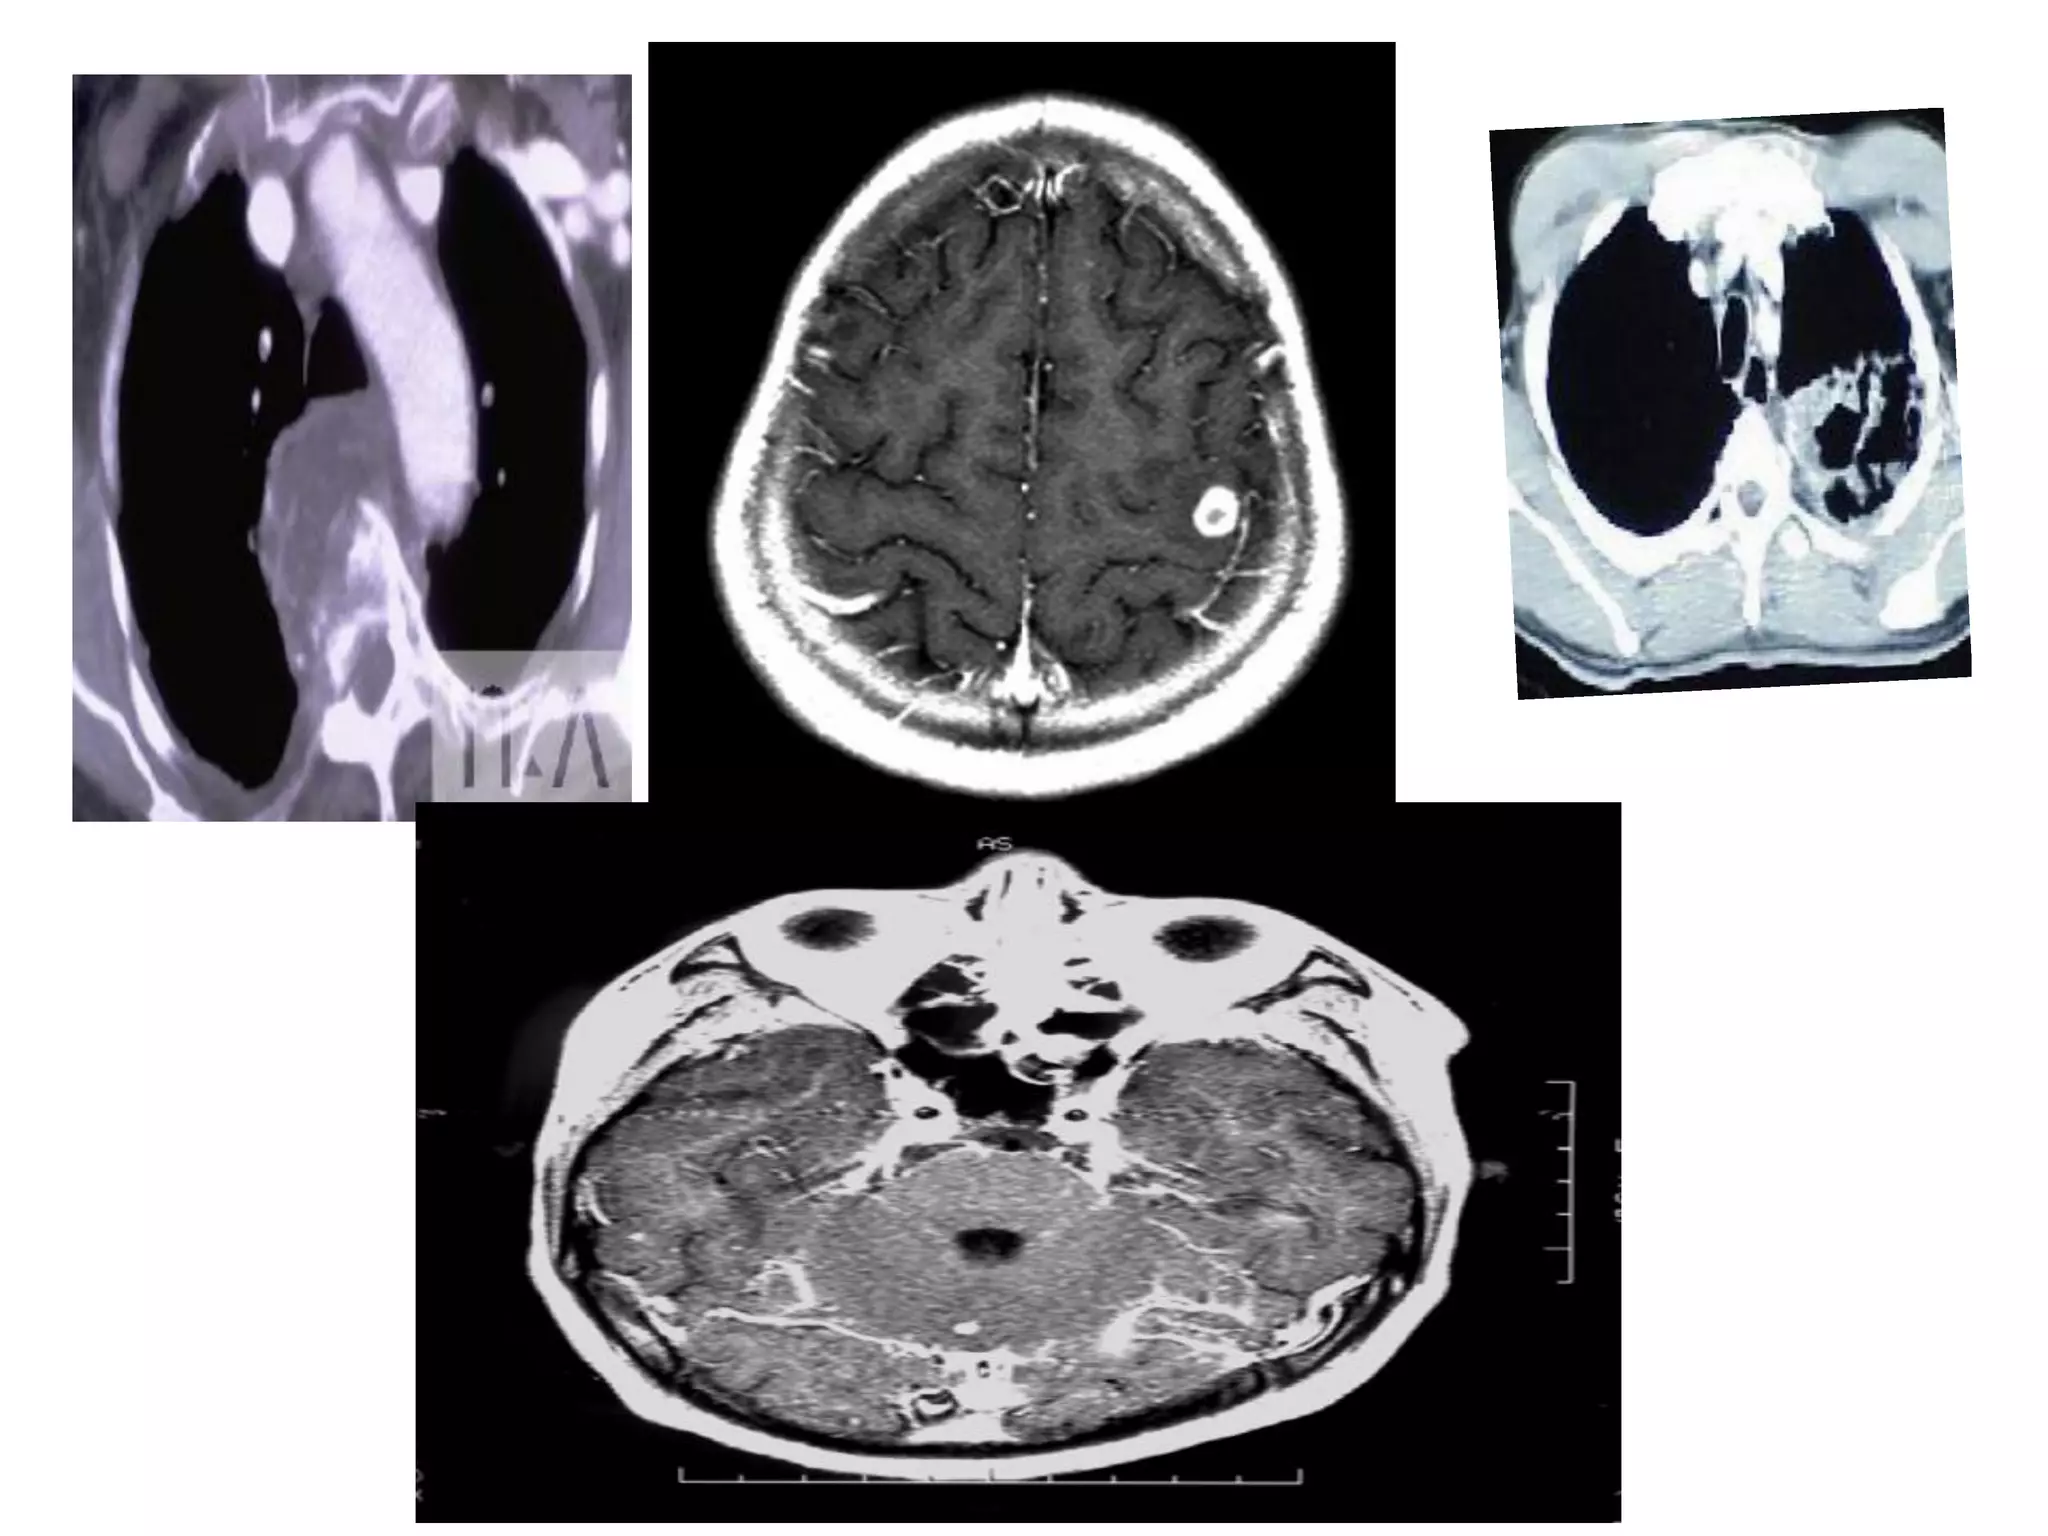

CT Scan and MRI Scan in the

diagnosis of TB

􀂄 The advent of CT and MRI imaging in

the last two

decades has redefined the approach in

analysis of

various diseases including TB.*

􀂄 CT and MRI have shown several

advantages over

conventional radiology in early diagnosis

and follow-up

of TB in different parts of the body.

*Buxi TBS Indian J Pediatr 2002;69:965-972

Pulmonary TB :

Lobar Pneumonia

􀂄

CT is superior than plain CXR in picking

up the

consolidation, atelectasis and the hilar LN

thereby

making the diagnosis easy.

􀂄 MRI reveals some of these changes,

however, CT is

the diagnostic modality of choice in such

cases.

Bronchopneumonia

On CT it is usually B/L and widespread,

not always

symmetrical involvement of lungs.

Hilar and Mediastinal

Lymphadenopathy

CT and MRI depict the hilar and

mediastinal LN

equally well.

􀂄 Calcification in the nodes is however

better seen on

CT.

􀂄 Necrosis is seen as focal areas of low

attenuation on

a CECT.

􀂄 On MRI focal necrosis is seen as areas

of increased

signal intensity on T2W images.

EBTB

HRCT is sensitive in the detection of

early

endobronchial spread of disease.

Miliary TB

􀂄 Earliest form of miliary TB is detectable

on HRCT.

􀂄 Coalescing nodules result into patchy

irregular

opacities and HRCT shows this variation

effectively

and has been described as “snowstorm

appearance”.

􀂄 HRCT shows cavitation, which is not

evident on plain

CXR.